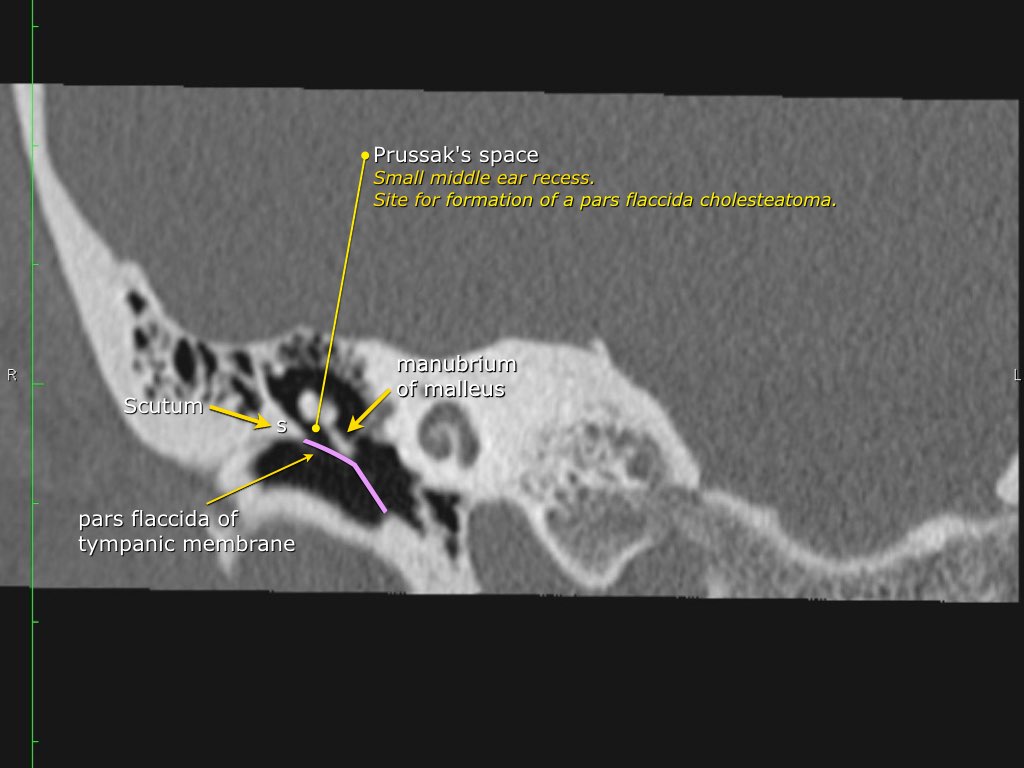

được tạo thành chủ yếu bởi màng nhĩ. Scutum (mảnh xương hình khiên) là gờ xương nằm ở phần trên hay còn gọi là pars flaccida của màng nhĩ.

Pars flaccida là phần trên mỏng manh của màng nhĩ, liên quan đến rối loạn chức năng vòi nhĩ và cholesteatoma.

Scutum

Đây thường là cấu trúc xương đầu tiên bị bào mòn do cholesteatoma, hình thành bởi sự co kéo vào trong của pars flaccida màng nhĩ vào vùng thượng nhĩ.